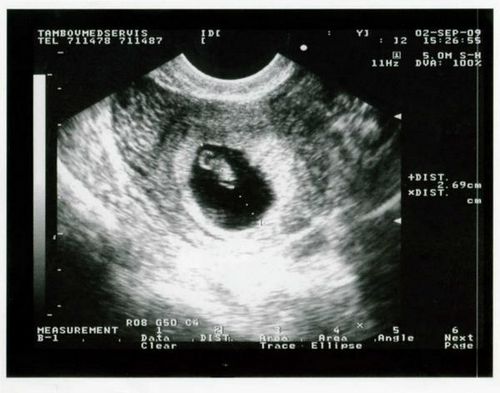

На 6 тижні вагітності по фото УЗД розмір плода встановить абсолютно чітко - це зовсім малесеньке, але вже цілком жива істота. Розмір плода фото УЗД показує дуже добре. Він досягає, всього на всього, 1,5 см. Саме на шостому тижні починають формуватися нервові закінчення в ручках і ніжках, а нервові клітини займають свої місця по всьому організму. Це говорить про те, що малюк скоро почне все відчувати, і буде поступово вчитися рухатися. За допомогою УЗД на цьому тижні вагітності лікар перевірить важливу особливість - як розвивається головний мозок плоду. До цього часу всі три частини «розумового відділу» дитини повинні бути сформовані. Фото УЗД допоможе виключити патології. Розмір плода фото УЗД для досвідченого лікаря може багато про що рассказать.Особенно це важливо, якщо є сумніви в правильному розвитку. З'являються невеликі пухирці, які незабаром стануть чудовими очима. Дивно, але зір - це той важливий орган, який буде формуватися протягом всієї вагітності і завершиться тільки після пологів. Починають формуватися легкі. В організмі все відбувається поступово, для кожного процесу є свій термін. Але завдяки таким знанням, ви можете, нарешті - то усвідомити, що всередині вас перебуває справжнє живе диво - ваш майбутній малюк. І нехай зараз - на шостому тижні, він зовсім не схожий на немовля, він вже є таким.

Розмір плода фото УЗД на даному терміні вагітності показує чітко і ясно. Але крім того УЗД в першому триместрі вкрай важливо для встановлення наявності патологій і загроз для життя як матері так і ребенка.Но все ж варто пам'ятати і про те, що не варто робити фото УЗД без показань лікар, а просто з цікавості побачити майбутню дитину. Справа в тому, що навіть якщо ви хочете побачити свою майбутню дитину цьому тижні вагітності, то вам це навряд чи вдасться.

Фото УЗД покаже, що на цьому тижні протікання вагітності розмір дитини досягає невеликої горошини. Але завдяки тому, що медицина сьогодні пішла далеко, УЗД може встановити розмір плода з точністю до міліметра. Як відбуваються виміри?

Для початку у малюка необхідно знайти куприк і визначити тім'яну зону. На фото УЗД це буде абсолютно невелику відстань, але все ж і його можна виміряти. Відстань між цими зонами називається довгою плода і на шостому тижні вагітності досягає всього пари міліметрів.

Фото УЗД розмір плода визначає точно і це важливо для першого триместру. Саме перше проведене УЗД допоможе лікарю встановити найбільш точний термін пологів. Це важливо в тому випадку, коли у вагітної до пологів не була регулярний або непостійний менструальний цикл або вона просто не пам'ятає необхідних дат. В основному, на шостому тижні УЗД проводиться для того, що б встановити достовірність вагітності - її наявність. До цього терміну матка починає збільшуватися і фото УЗД фіксує ці зміни. Для того, що б більш точно встановити розмір плода і термін вагітності за допомогою УЗД також проводять дослідження плодового мішка. Допоможе у встановленні термінів і серцебиття вашого малюка. Апарат УЗД вловлює скорочення сердечка, виводить їх на екран і динамік. Мама може насолоджуватися, а лікар завдяки цим звукам встановить термін розвитку ембріона, яким повинен бути розмір плода і визначить за допомогою УЗД безпосередньо сам термін вагітності і дату можливих пологів.